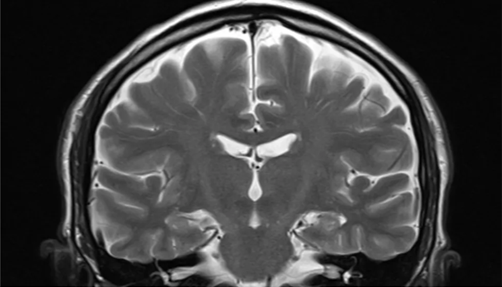

Astfel, cu câteva luni în urmă, în luna iulie a acestui an, o echipă de oameni de știință din Statele Unite, condusă de Ahmad Hariri, profesor de psihologie și neuroștiințe la Universitatea Duke, a publicat în revista Nature Aging rezultatele analizei lor comparative a îmbătrânirii biologice bazate pe RMN-uri ale creierului.

Acesta este un nou mod de a măsura cât de repede îmbătrânește o persoană și, prin urmare, de a-i prezice longevitatea, deoarece îmbătrânirea mai rapidă crește riscul de a suferi de multe boli, inclusiv diabet, boli de inimă, accident vascular cerebral și demență și, prin urmare, de moarte timpurie.